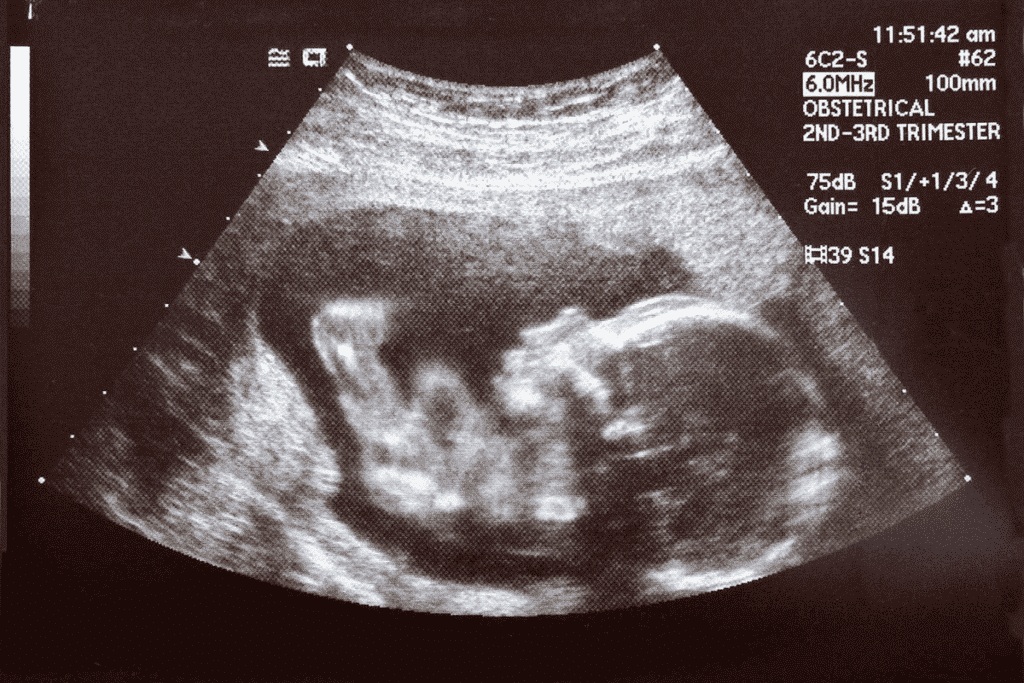

What Does a 7 Week Ultrasound Look Like?

At 7 weeks, an ultrasound can show important details about your pregnancy. We can see key structures that mean your pregnancy is healthy.

Normal Appearances and Variations

A normal 7-week ultrasound shows the gestational sac, yolk sac, and the fetal pole. The gestational sac is the first sign of pregnancy seen on an ultrasound. It looks like a small, fluid-filled area in the uterus.

The yolk sac gives nutrients to the embryo before the placenta grows. It looks like a small circle in the gestational sac. The fetal pole, or early embryo, is seen by 7 weeks. It is attached to the yolk sac.

Image Quality and Limitations

The quality of the ultrasound image can change due to several things. These include the sonographer’s skill, the ultrasound equipment’s quality, and the fetus’s position.

“The clarity of the ultrasound image is key for accurate diagnosis. Things like maternal BMI and fetal position can impact image quality.”

Even though a 7-week ultrasound is valuable, there are limits. It can be hard to see a fetal heartbeat or measure the crown-rump length if the fetus is in a bad position.

Knowing these things can help manage your expectations and reduce worry during the ultrasound. It’s a good idea to talk to your healthcare provider about any concerns or questions. This can help you understand your situation better.